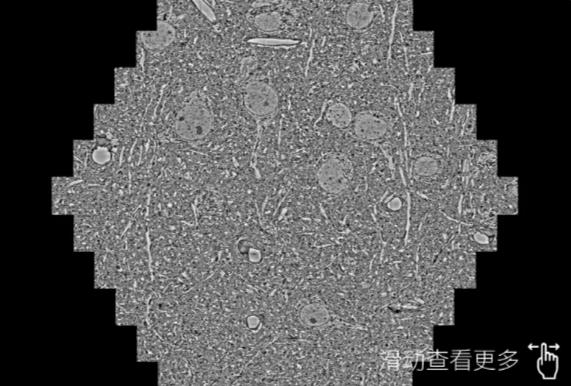

鼠脑切片。左图使用甘肃蔡司甘肃扫描电镜MultiSEM706对165μmx143pm面积区域成像,耗时仅需1.5秒。右图为鼠脑切片中30μm区域放大效果。样品由芝加哥大学B.Kasthuri提供。